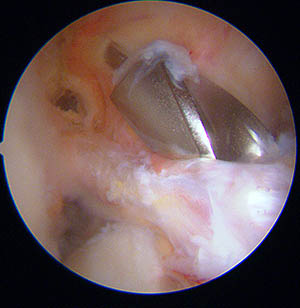

Image sous arthroscopie d'un cyclope : les fibres rompues du ligament croisé antérieur gènent l'extension complète du genou.

La photo ci-dessous, montre une vue sous arthroscopie de la greffe à la fin de l'intervention. Elle sort du tunnel tibial dans les restes du l'ex ligament croisé antérieur (technique appelée SAMBA).

Le but de cette technique (que tous les chirurgiens utilisent a priori) est de préserver tous les tissus restants, car ils sont d'une part, remplis de "mécano-récepteurs" utiles pour la proprioceptivité, et d'autre part, ces tissus vascularisés en enveloppant la greffe, vont participer à la revascularisation ultérieure de la greffe.